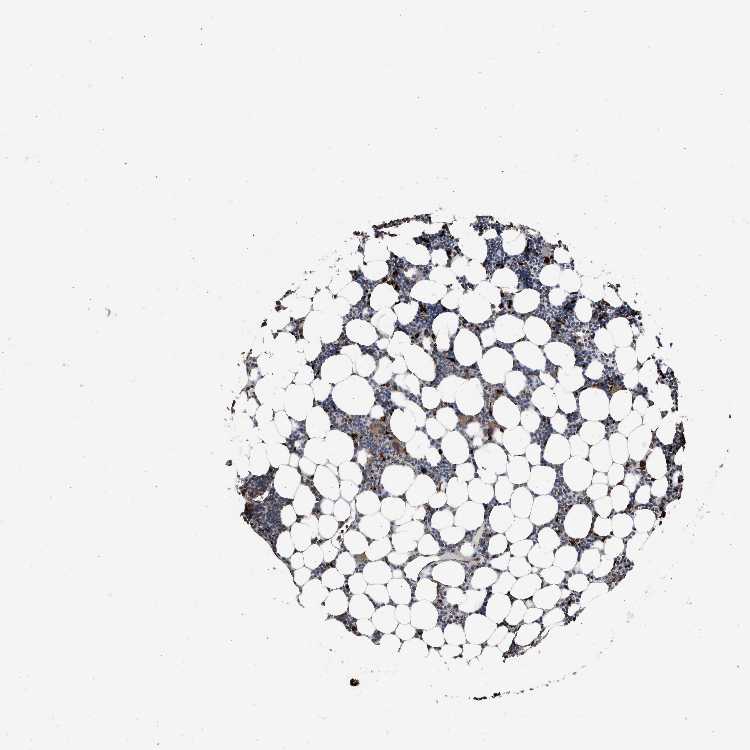

TISSUE PRIMARY DATA BONE MARROW Show tissue menu

BONE MARROW - Antibody stainingi

Antibody staining in the annotated cell types in the current human tissue is reported as not detected, low, medium, or high, based on conventional immunohistochemistry profiling in selected tissues. This score is based on the combination of the staining intensity and fraction of stained cells.

Each image is clickable and will lead to virtual microscopy that enables deeper exploration of all samples and also displays staining intensity scores, fraction scores and subcellular localization as well as patient and tissue information for each sample.

Antibody CAB017112

Hematopoietic cells Low